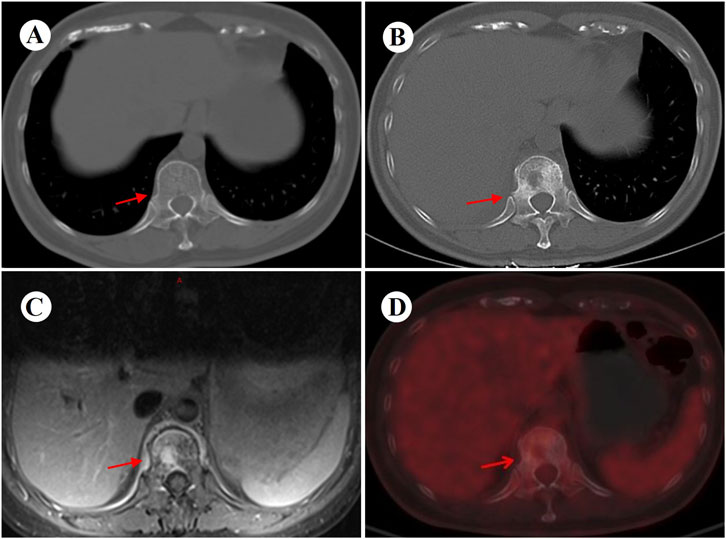

At 4 weeks postoperatively, the patient developed CTCAE v5.0 grade 3 dermatological toxicity characterized by a pruritic rash. This adverse event persisted despite stepwise dose reduction (from 225 mg to 150 mg) and combination therapy with systemic corticosteroids and antihistamines (Figure 2). Notably, serial molecular residual disease (MRD) assessments were negative at 10 days and 3 months postoperatively. However, surveillance imaging at the 3-month follow-up demonstrated osteolytic destruction of the T12 vertebral body and adjacent structures, radiologically consistent with osseous metastasis (Figure 3). Re-staging indicated rT0N0M1 (Stage IV) disease. For oligometastatic bone disease, local surgery or radiotherapy may be considered alongside ongoing targeted therapy. The patient, however, declined further local interventions, including radiotherapy or surgical management, citing diminished confidence following early disease progression.

Figure 3. Images before and 3 months after surgery. (A) Preoperative chest CT (bone window) performed on 13 March 2024 shows an intact T12 vertebral body and attachments. (B) Follow-up CT (bone window) at 3 months postoperatively reveals new osteolytic destruction of the T12 vertebral body and attachments. (C,D) Subsequent MRI and PET-CT further confirm metastatic involvement of the T12 vertebra, with concordant imaging findings. CT, computed tomography; PET, positron emission tomography; MRI, magnetic resonance imaging.